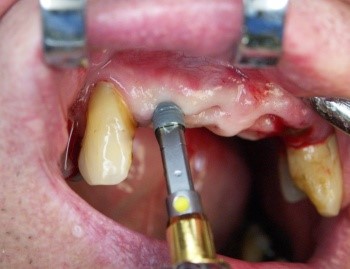

На фото представлены все этапы имплантации зубов от исходного состояния пациента до конечного результата.

Имплантологи стоматологической клиники «Аркобалено» также проводят работы, когда в деснах отсутствует костная ткань. Такие случаи решаются с помощью наклонных имплантатов без необходимости восстановления костной ткани.

Имплантация в стоматологии «Аркобалено» при пародонтозе зубов, представлены все этапы имплантации под ключ.